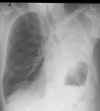

X rays?

* different tissues attenuate the beam to varying degrees depending on atomic constituents * The image starts all white.  If x-rays reach the detector that part of the image turns black.

heart on an XR?

52

Lungs on an XR